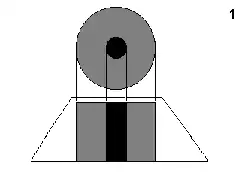

La figura '1' representa el resultado en imagen de una sola incidencia o proyección (vertical, a 90º). Se trata de una representación esquemática de un miembro, por ejemplo un muslo. El color negro representa una densidad elevada, la del hueso. El color gris representa una densidad media, los tejidos blandos (músculos). |